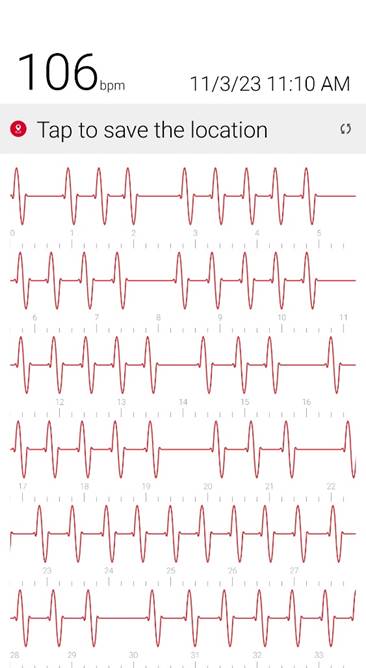

Initial ID consult diagnosed local tetanus based on clinical symptoms and recommended oral Metronidazole 500mg every 6 hours as an outpatient. Autonomic involvement developed with tachycardia and cardiac arrhythmia, along with episodes of sudden sweating. Loud noises made twitching/spasms worsen. Intermittent twitching continued to be present bilaterally in the body, face, jaw & tongue. Symptoms were suppressible with benzodiazepine. Tetanus IM IG 500 IU was recommended and obtained. After initial 2 week course of metronidazole was discontinued symptoms worsened again when patient would walk. Multiple trials of oral Metronidazole 500mg every 6 hours were attempted with some improvement while on the antibiotic but then return and worsening of symptoms again once antibiotic was discontinued.

3) Cardiac Arrhythmia / Heart Block occurs during generalizations

When antibiotic is discontinued or with increased walking, rhythm returns to normal when antibiotic is restarted after a few days.